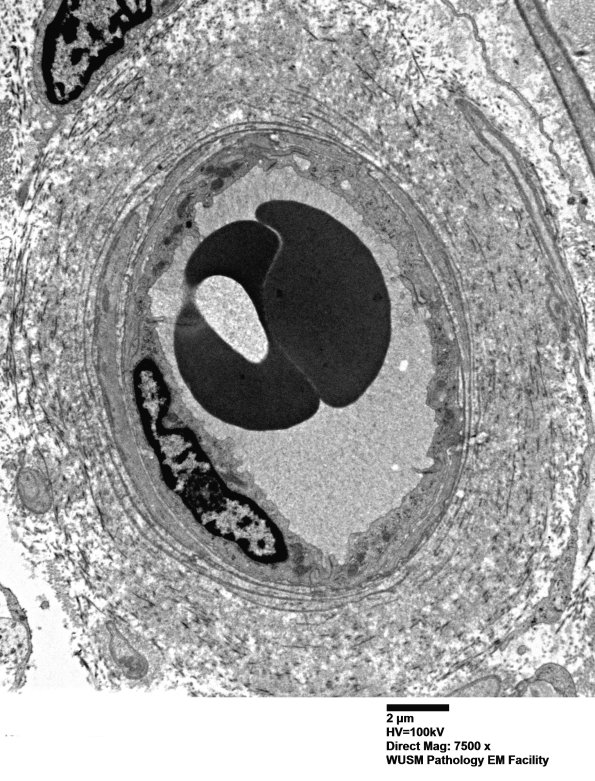

Washington University Experience | VASCULAR | Hypoxia-Ischemia, fetal-neonatal | White Matter | 17B4 (Case 17) HIEM EM018 - Copy

17B4 (Case 17) HIEM EM018 - Copy